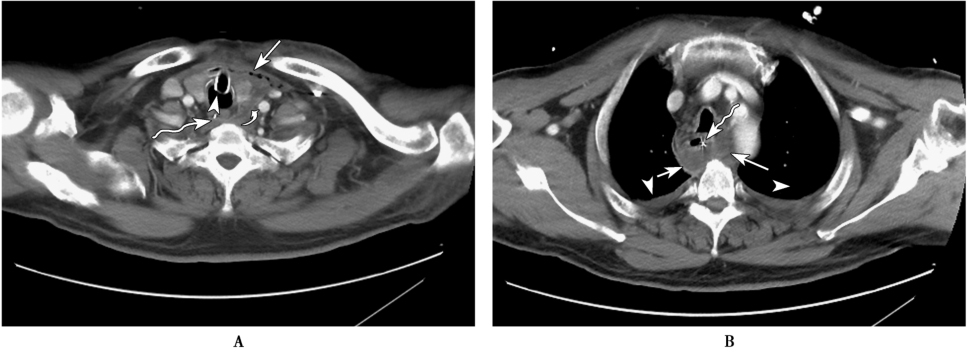

图2 纵隔脓肿

患者,男,58岁,发热1周。A.胸部CT增强扫描纵隔窗示甲状腺左叶左旁与左侧颈总动脉间(白弯箭)液性渗出影,纵隔内多发游离气体密度影(白箭),气管(白箭头)及食管内(波浪箭)分别见插管影;B.胸部CT增强扫描纵隔窗示食管左侧及后方(白箭)包裹性液性渗出影,囊壁轻度强化,食管内(波浪箭)见置管影,双侧胸腔内少量积液(白箭头)。